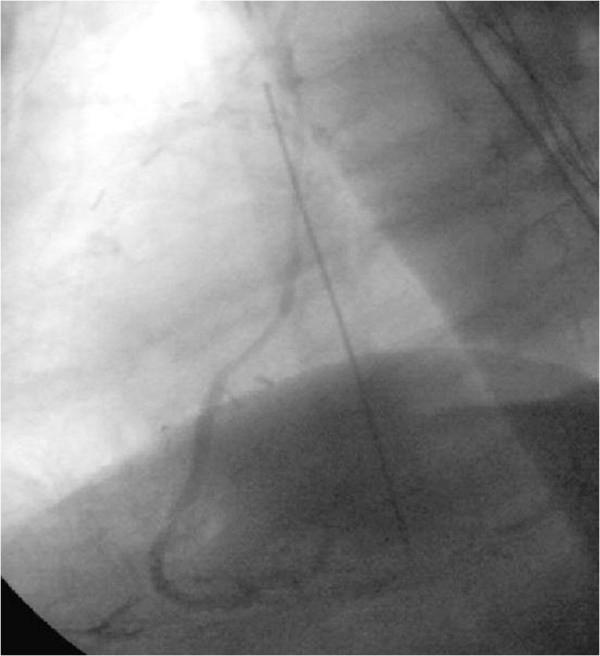

Patients with extensive coronary artery disease often require re-do coronary artery bypass grafting. However, autologous bypass material is sometimes sparse. Since long term patency of arterial graft material is superior to venous bypass grafting, we developed a technique to perform re-do total arterial coronary artery bypass grafting extending the right internal thoracic artery (RITA) with the radial artery (RA) in an end to end fashion to gain the needed length in patients with and without an open left thoracic artery (LITA).

The operational technique of elongation of the internal thoracic artery with the radial artery proved to be safe and feasible with acceptable operation times for a re-do procedure. We recommend this as an additional option to existing methods to perform a complete arterial revascularization mainly in patients with open left internal thoracic artery to LAD bypass.